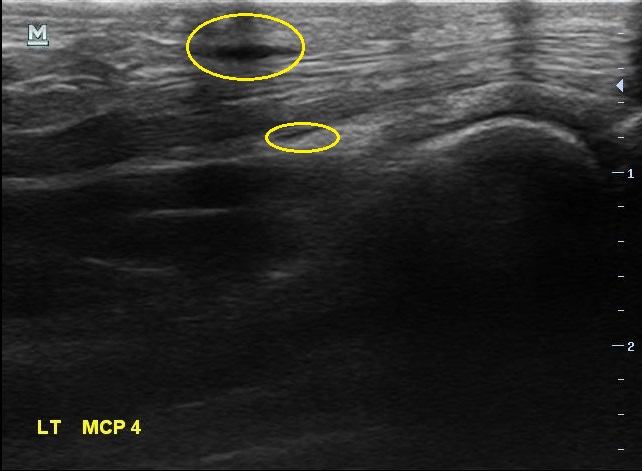

X-ray 검사상에는 특별한건 보이지 않습니다. 초음파 검사에서는.... 4번째 손가락을 굽혀주는 힘줄(4th flexor digitorum tendon)에 염증이 생겨있습니다.

골프에 너무 빠져서 아파도 참고 치셨다는 분... 초음파 검사를 다시 해보니...

2주 전보다 힘줄에 염증이 훨씬 심해져 있었습니다. 그리고

이번에는 한 부위만이 아니라 손가락 굽힘 힘줄을 따라 전체적으로 염증이 퍼져있습니다.